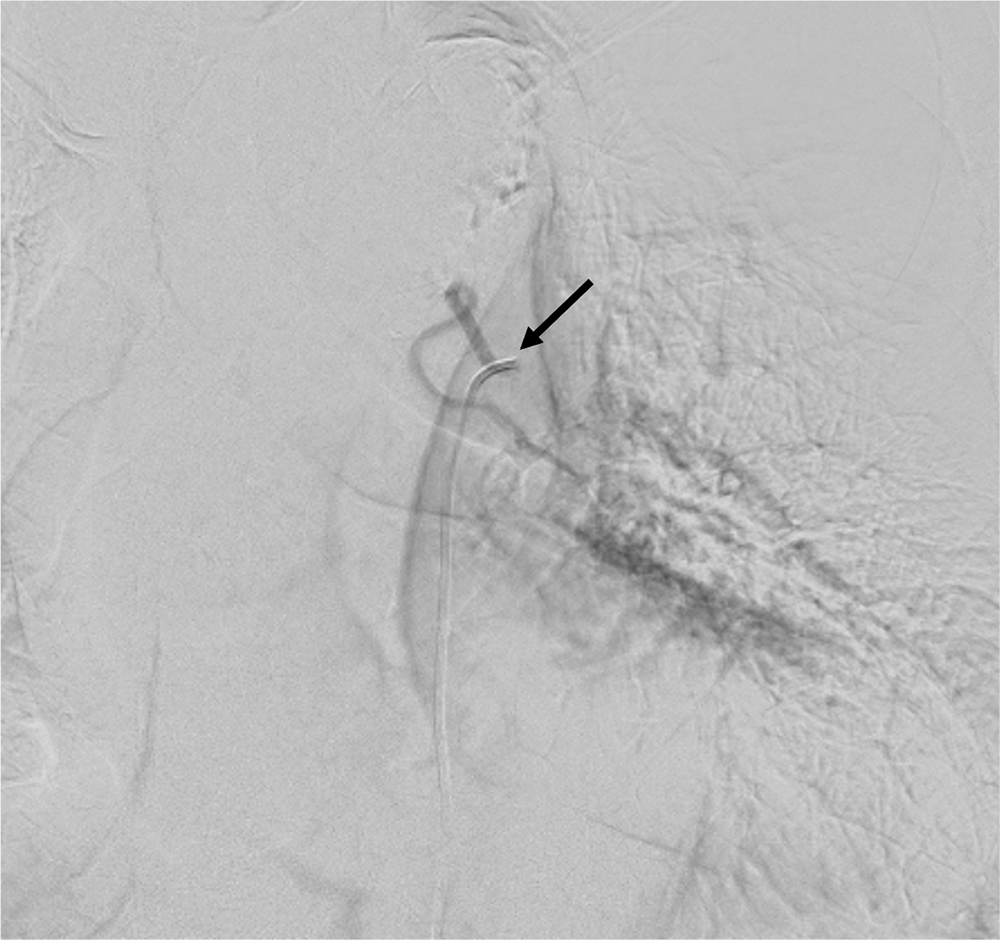

症例は左膿胸に対し術後の既往がある患者。少量の喀血が継続することを主訴に呼吸器内科を受診し、造影CTが施行された。左肺下葉にはすりガラス陰影とconsolidationがみられ、喀血の吸い込み像と思われた。左気管支動脈は拡張していたが、起始部で高度狭窄が疑われた。BAE施行目的に当院放射線科に紹介された。

今回は臨床的に左気管支動脈が原因として疑われていたが、起始部が極めて細径であった。カテーテル治療が困難と思われたが術前造影CTを施行し、thin sliceにて起始部のレベル・分岐方向を同定することができた。このことで必要十分な塞栓術が施行され、治療を完遂することができた症例である。